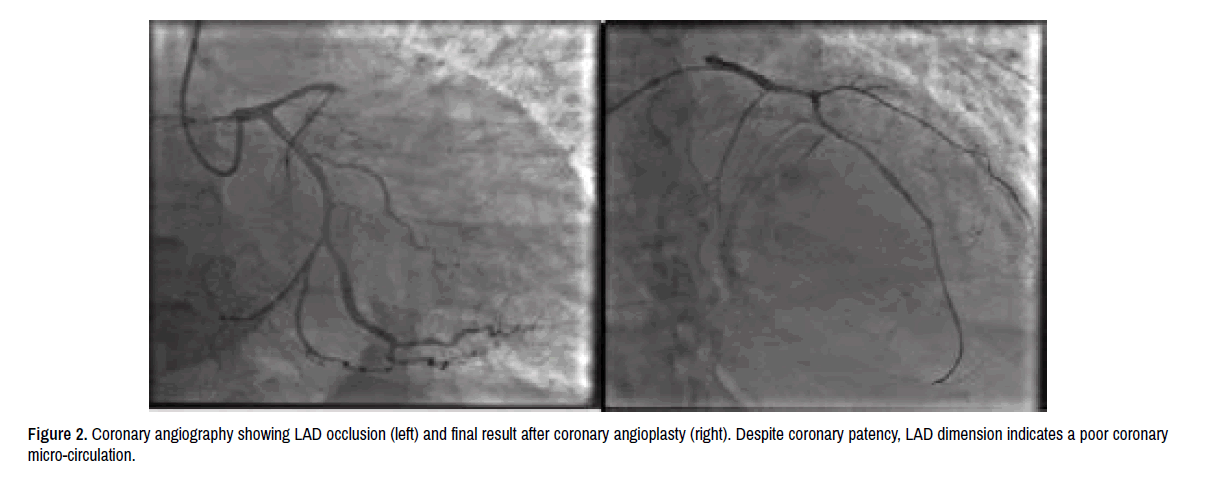

Electrocardiogram showed sinus tachycardia (115 bpm), ST-elevation in V1-V5 leads with Q-waves (Figure 1). Pulmonary edema and bilateral pleural effusion were found at chest X-ray. Coronary angiography showed total occlusion of mid Left Anterior Descending (LAD) coronary and 75% stenosis of mid Right Coronary Artery (RCA). After thrombus aspiration, LAD angioplasty and drug-eluting stenting (3.0 × 22 mm), final distal LAD patency was sub-optimal (Figure 2), presumably because of very late coronary reperfusion.

Figure 2. Coronary angiography showing LAD occlusion (left) and final result after coronary angioplasty (right). Despite coronary patency, LAD dimension indicates a poor coronary micro-circulation.